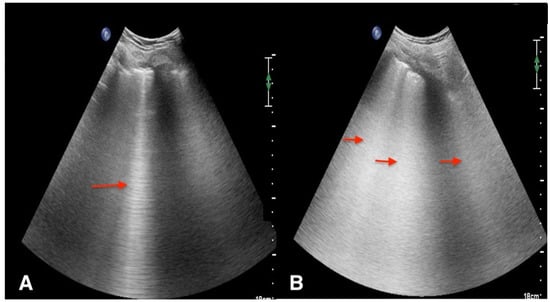

Real Images

Pneumothorax